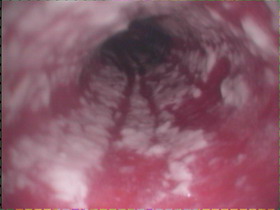

(1)胃鏡檢查:是確診黴菌型食管炎的唯一方法,鏡下食管黏膜呈現水腫、充血、糜爛、潰瘍,觸之易出血。黏膜表面覆蓋白色斑點或偽膜。進行活檢及細胞刷塗片和培養,若塗片見有黴菌菌絲,活檢組織見有菌絲侵入上皮方可確診